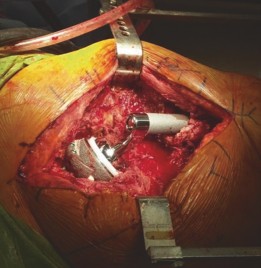

Main steps : (1) Prostalac removal. (2) Preparation of the anatomic acetabulum with reamers to determine the cup size. (3) Size acetabular rim defect and use reamers to size defect and prepare a smooth surface. (4) Place augment with provisional pins with the trial cup in place. (5) Add screws to augment. (6) Apply cement to the augment and impact acetabular component. (7) Prepare femur and insert stem (Figs. 19.15 and 19.16).

--- Fig. 19.15 Intraoperative view of the acetabular rim defect and augment with cement at the component interface. Modular Wagner femoral revision stem with severe proximal femoral bone loss #### Intraoperative Challenges

Challenges and solutions: Need to anticipate the loss of acetabular rim bone and have appropriate implants available. Poor bone quality required very delicate reaming of the acetabulum and the rim defect.